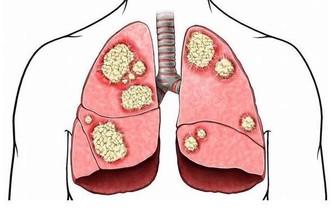

脂肪酸釋放難以分解,營養不良同樣會得脂肪肝

連雲港市第一人民醫院健康管理專家劉曉光在詢問了陳先生情況后,做出了解釋。其實脂肪肝分為酒精性脂肪肝和非酒精性脂肪肝,酒精性脂肪肝是長期飲酒造成的,營養過剩和營養不良都可能導致非酒精性脂肪肝。

據統計,約有22%的素食者會得脂肪肝,而這些人也大多是正常體型。劉曉光醫師稱,人體中所需要的能量主要來自三大營養物質,脂肪、蛋白質和碳水化合物。像陳先生這種純素食者,不吃魚肉蛋等營養物質,也就是少了動物蛋白質和脂肪來源,人體的白蛋白合成減少,就需要分解脂肪組織來維持營養均衡,大量的脂肪酸從脂肪組織中釋放進入肝臟后,而這種脂肪在肝臟中不易被分解,若不能及時排出,肝臟中的脂肪堆積過多,長期以往,就形成了脂肪肝。

不只是素食主義者有患病隱患,曾經有社區在湖北武漢對歸元寺、鐵佛寺的兩寺僧人進行體檢,結果令人大吃一驚:受檢的30名僧人中,接近一半的僧人的肝內總脂肪量佔到肝重的5%-10%,達到輕度脂肪肝的標準。